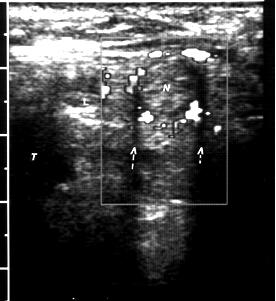

Ecografie tiroidiana : LD 6,1/3/2,6 cm, ecostructura hipoecogena, intens neomogena prin prezenta in 1/3 superioara a unui nodul de 2,1/1,8cm, hipoecogen, intens vascularizat si 1/3 inferioara a unui alt nodul de 1,3/1 cm, hipoecogen, vascularizat; restul lobului cu vascularizatie usor redusa.

Istm 0,4cm

LS 4,9/2/1,8 cm, hipoecogen, neomogen prin prezenta in 1/3 medie a 3 noduli hipoecogeni infracentimetrici, vascularizati si in 1/3 inferioara a unui nodul de 0,9/1,2 cm, hipoecogen, intens vascularizat ; restul lobului cu vascularizatie normala.

Fara adenopatii laterocervicale vizibile ecografic.